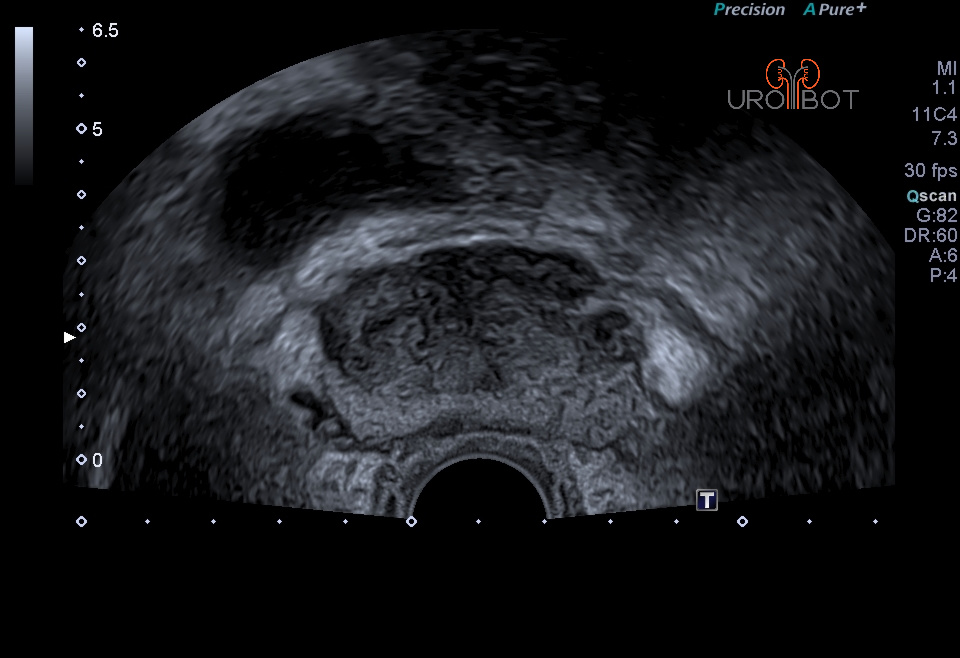

In der Klinik für Urologie am Knappschaftskrankenhaus Bottrop steht seit 10/2017 ein neues Gerät zur Verfügung, welches die Bilder eines 3-Tesla-MRT-Gerätes mit denen eines High-End-Ultraschallgerätes fusionieren kann. Eine Spezialsoftware ermöglicht eine dreidimensionale Rekonstruktion der Prostata, in der die zuvor markierten auffälligen Areale in ihrer räumlichen Lokalisation sichtbar gemacht werden können. Durch die bessere Detektionsrate bei der MRT-Untersuchung lassen sich somit auffällige Areale auf die konventionellen Echtzeit-Ultraschallaufnahmen spiegeln, sodass dadurch eine millimetergenaue Gewebeprobe auffälliger Areale in der Prostata erfolgen kann. Dadurch kann die Entdeckung von bösartigen Prostatatumoren entscheidend verbessert werden.

Das Video zeigt eine sonographische Untersuchung der Prostata, durchgeführt über eine sogenannte transrektale Ultraschallsonde.